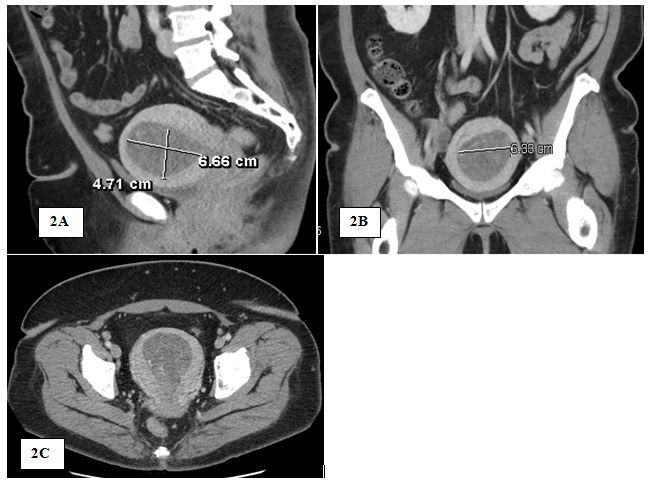

Patient was lost to follow-up until she presented in May 2018 for irregular bleeding and endometrial biopsy showed endometrial hyperplasia with atypia suspicious for adenocarcinoma; endocervical curettage and endocervical polyp showed similar pathology. Pap screen and HPV were negative for intraepithelial lesion or malignancy; CA-125 was 43.4. Pelvic sonogram showed the uterus (11.3 by 7.6 by 8.5) with an endometrial mass (10.5 by 5.8 by 6.6) (Figure 1). In addition, there was a 19-mm cyst in the right ovary (Figure 1). On review of the sonogram, the endometrial mass is heterogenous and extended into the endocervical os (Figure 1). Concurrent chest x-ray was within normal limits with no abnormalities; CT of the chest, abdomen, and pelvis (Figure 2) was negative for chest and liver metastasis and hydronephrosis; positive for 7-mm paraaortic node, 9-mm pelvic node, right ovarian cyst (2.8-cm), and an endometrial mass (6.7 by 6.4-cm). Physical exam showed midline cervix 2.0 cm in diameter, soft but with 4 by 5 mm ass protruding from the cervical os. Uterus is 12 by 10 by 8 cm anterior not tender. Adnexa were not appreciated and no nodularity in the cul de sac. The patient was started on Megace 40mg daily. At this time, hysterectomy, bilateral salpingo-oophorectomy and staging were indicated.

Figure 2 Computed tomography (CT) of Pelvis: sagittal View (2A); Coronal View (2B); and Transverse View (2C), showing 6.7×6.4×10cm hypodense mass in the endometrial cavity compatible with known uterine cancer.